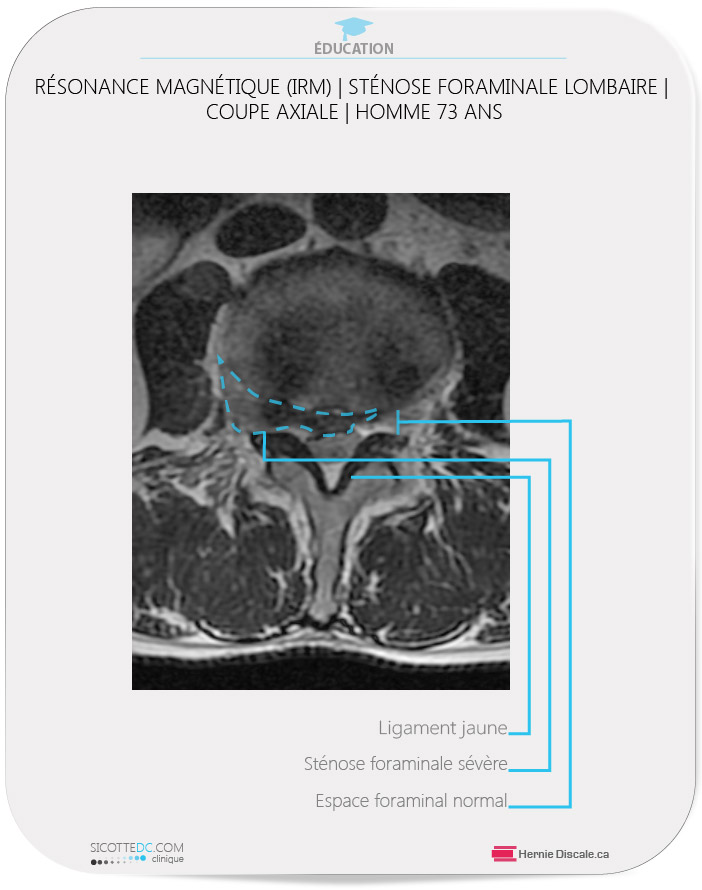

À l’arrivée à notre clinique, ce patient de 73 ans était sous l’effet de forte dose de morphine pour contrôler la douleur. Il ambulait avec difficulté. Le patient possédait une IRM au moment de la consultation. L’examen physique a révélé les faits suivants : sensation des membres inférieurs intacte, douleur en prédominance à la jambe droite et le fessier droit. Après dix jours de traitements avec la méthode Cox®, le patient pouvait dormir et marcher normalement.

RÉSONANCE MAGNÉTIQUE (IRM) | EXEMPLE DE STÉNOSE FORAMINALE LOMBAIRE | COUPE AXIALE

INTERPRÉTATION

- Ligament jaune : Le ligament jaune est hypertrophié. Ceci diminue la distance antéropostérieure du canal vertébral.

- Sténose foraminale sévère : La hernie discale importante déborde vers le foramen causant un pincement du nerf rachidien.

- Espace normal : Du côté opposé, l’espace est normal.